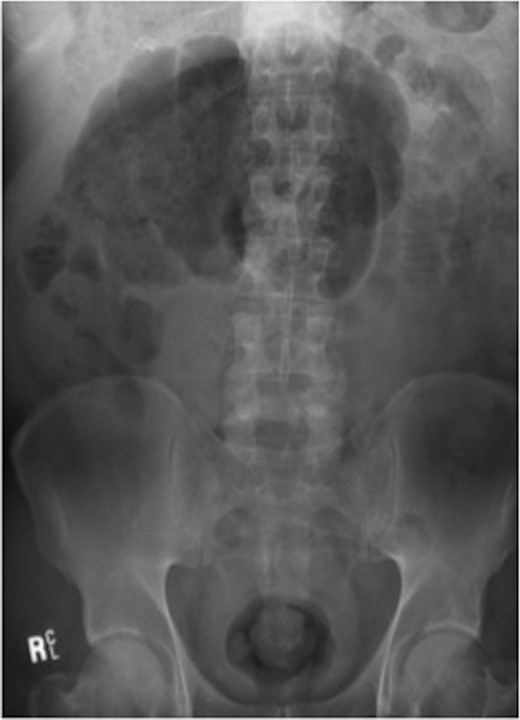

A gastrografin enema (Fig. 4) failed to demonstrate any flow beyond the mid-transverse colon. A presumptive diagnosis of transverse colon obstruction was made and the patient was taken to theatre.

Gastrografin enema (Case 2) demonstrating no flow beyond the mid-transverse colon.